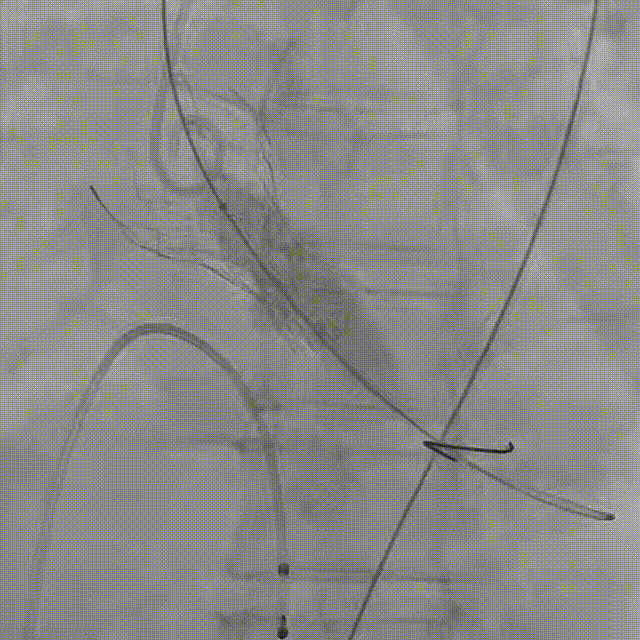

患者病史 主诉:发作性胸闷憋喘半年,加重伴呼吸困难2周。 现病史:患者半年前无明显诱因出现胸闷、憋喘,伴有下肢水肿,2周前上述症状明显加重,夜间不能平卧,痰中带血丝,为进一步诊治再次来我院,门诊以"心力衰竭"收入院。 既往史:肾功能不全、心房颤动 心脏超声提示:LVEF:0.54 1.主动脉瓣病变;2.主动脉瓣狭窄(重度)并反流(中度);3左室壁节段性运动不良;4.升主动脉扩张、双房扩大、左室肥厚;5.二尖瓣硬化并反流(中度);6.三尖瓣反流(轻-中度);7.肺动脉瓣反流;8.肺动脉高压(轻度)PGmean=105mmHg,Vmax=635cm/s,瓣口面积0.27cm²。 术前CT评估 Type0型二叶瓣,重度钙化,钙化集中在瓣叶游离缘,右冠窦为著;左冠高度11.8mm,由于左冠窦部空间较小,左冠风险较高, 升主动脉扩张,最宽处50.5mm;主动脉瓣环水平夹角61.5°,横位心。主动脉弓角77.6°,锐角弓,外周入路在腹主及髂总处有大量散状钙化,胸主处有81.6°的迂曲。 手术策略 推荐右侧股动脉为主入路,左侧股动脉为辅入路,送snare辅助过弯,使用18F大鞘,推荐预装ProStyle A® AV23瓣膜,20mm球囊预扩,初始定位对齐真实瓣环瓣上5mm超高位初始定位释放,释放过程中使瓣膜自然下滑,到工作位观察瓣膜形态,最终理想位置0-瓣下3mm。 手术过程 Step1:右侧股动脉为主入路、左侧股动脉为辅入路,成功穿刺并送入 18F 大鞘; Step2:主动脉根部造影,瓣口限制重 Step3:Type 0 型二叶瓣畸形合并重度钙化,患者瓣口狭窄严重,同时横位心,不仅导丝跨瓣困难,导管更难进入;术者凭借精湛操作,将导丝顺利跨瓣,反复微调导管角度,最终导管顺利过瓣。 导丝精准跨瓣 Step4:20mm球囊跨瓣困难,snare辅助下球囊成功跨瓣,预扩有腰无漏,冠脉充盈良好。 Step5: snare辅助下成功跨瓣,可以看到系统过弓形态瓣膜仓柔软,过弓顺滑 输送系统过弓 Step6:初始定位瓣上5mm开始释放,释放部分后观察瓣架下缘内收明显,后回收系统重新定位 初始定位 底部内收 Step7:瓣膜完全释放前,血压一度降低,术者迅速调整器械,实现瓣膜迅速锚定,快速释放 完全释放 Step8:20mm球囊后扩 最终造影,位置(瓣下3mm)形态良好 手术难点 患者不仅有主动脉瓣重度狭窄,还叠加肾功能不全、心房颤动等基础疾病,术中血流动力学波动极易引发心功能衰竭。ProStyle A® 预装干瓣“开包即用” 的特性压缩了术者操作时间,80%可回收设计给了术者容错空间,而这些看似难以逾越的难关,最终被团队精湛的医术一一化解,术中对于导丝、导管、球囊等器械每一步的精准操控,再到突发状况的从容处置,无不彰显着团队深厚的专业积淀与顶尖的操作技艺。 结语 此次手术的圆满成功,不仅彰显了陈玉国、李传保教授团队在复杂结构性心脏病介入治疗领域深厚的专业造诣与攻坚克难的决心,也充分验证了ProStyle A®系统在应对复杂高难度病例时的卓越适用性与有效性。 作为扎根齐鲁、享誉全国的医疗高地,山东大学齐鲁医院始终赓续着这片热土的仁厚文脉,将“医道从德,术业求精”的院训精神镌刻在每一次诊疗实践之中。特别是在结构性心脏病诊疗领域,医院团队始终怀揣医者担当,勇攀医学高峰,不断以更前沿的技术突破,为危重患者点亮重获新生的希望。 专家简介 陈玉国 山东大学齐鲁医院(点击查看专家详细简历) 李传保 山东大学齐鲁医院(点击查看专家详细简历) · END ·